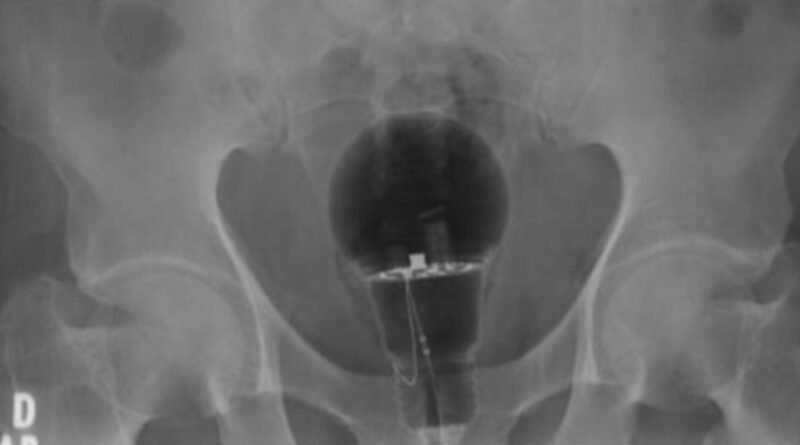

Os médicos fizeram exame no paciente e foi constatado que ele estava com uma lâmpada presa no reto. De acordo com veículos locais, o homem estava sofrendo dores há três dias.

No entanto, ele só procurou ajuda médica quando a dor ficou intensa. Depois dos médicos identificarem o problema, o homem comentou que não revelou o que era e nem foi antes para o hospital por medo de que sua esposa descobrisse o que havia acontecido. “O objeto não era palpável ao toque retal.

Material de corpo estranho”, escreveu no Twitter o gastroenterologista Julian Pylori, que divulgou uma imagem do raio-x. A TV Azteca informou que o objeto era de plástico e, assim, não estourou dentro do corpo do homem. A lâmpada foi removida pelos médicos e o paciente passa bem.